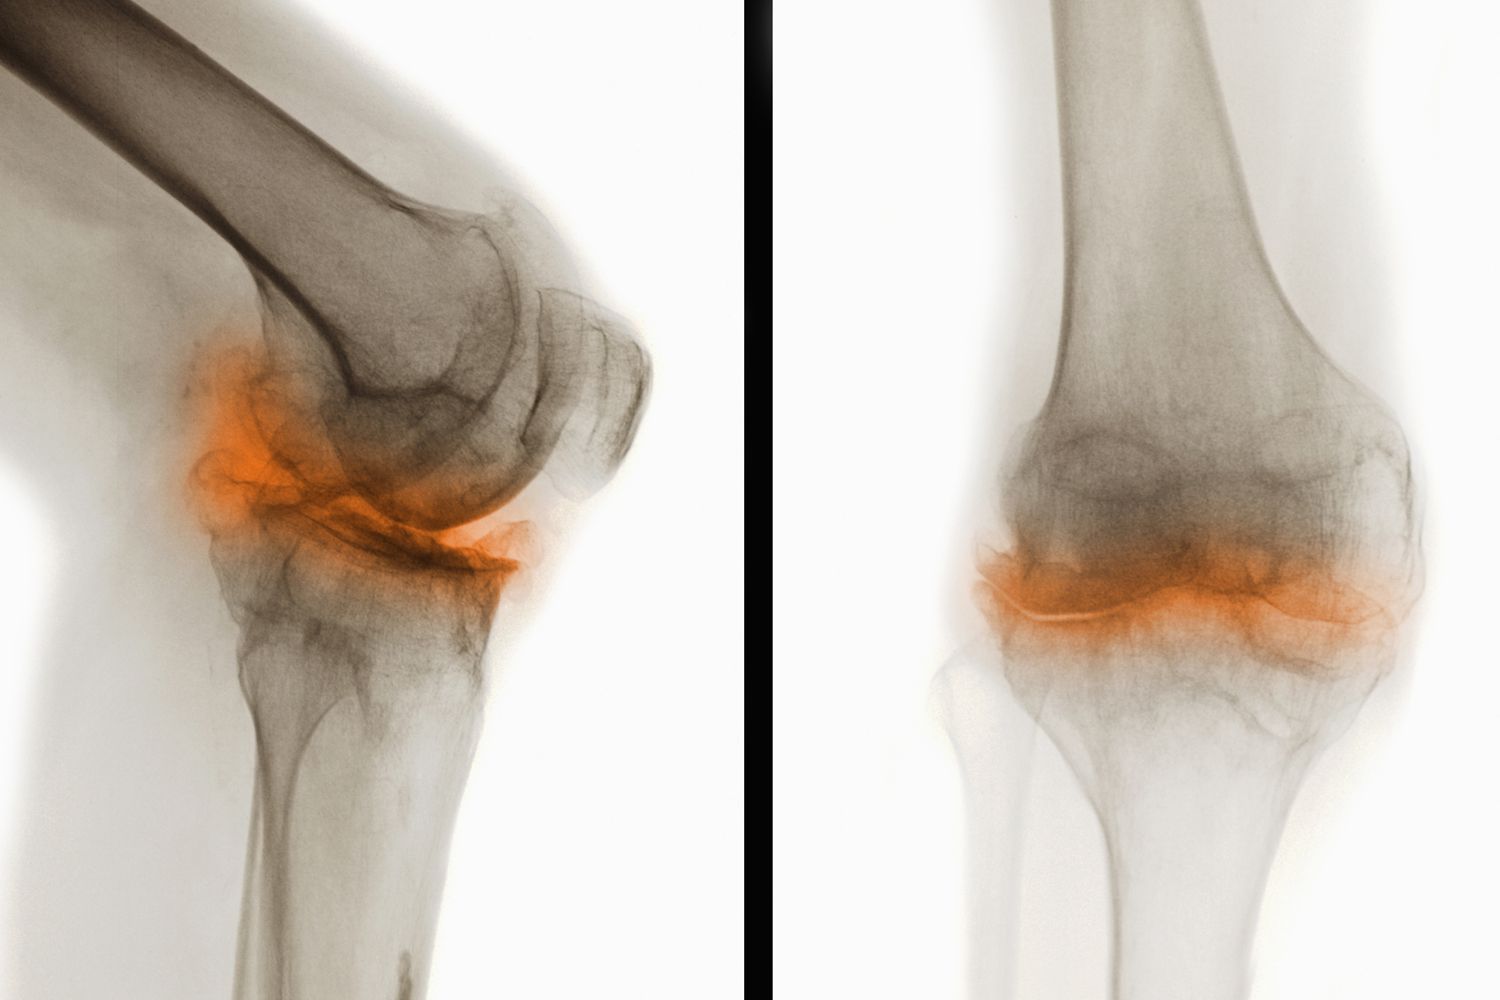

骨關(guān)節(jié)炎(Osteoarthritis,簡(jiǎn)稱OA)是一種常見的慢性退行性關(guān)節(jié)疾病,主要表現(xiàn)為關(guān)節(jié)軟骨的退化和破壞,導(dǎo)致關(guān)節(jié)疼痛、僵硬和功能障礙。這種疾病通常發(fā)生在中老年人群中,尤其是負(fù)重較大的膝關(guān)節(jié)、髖關(guān)節(jié)、脊柱及遠(yuǎn)側(cè)指間關(guān)節(jié)等部位。